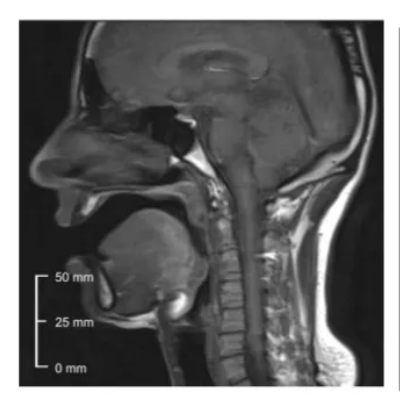

pharyngeal articulation

articulated with the root of the tongue moving towards the ball wall of the pharynx